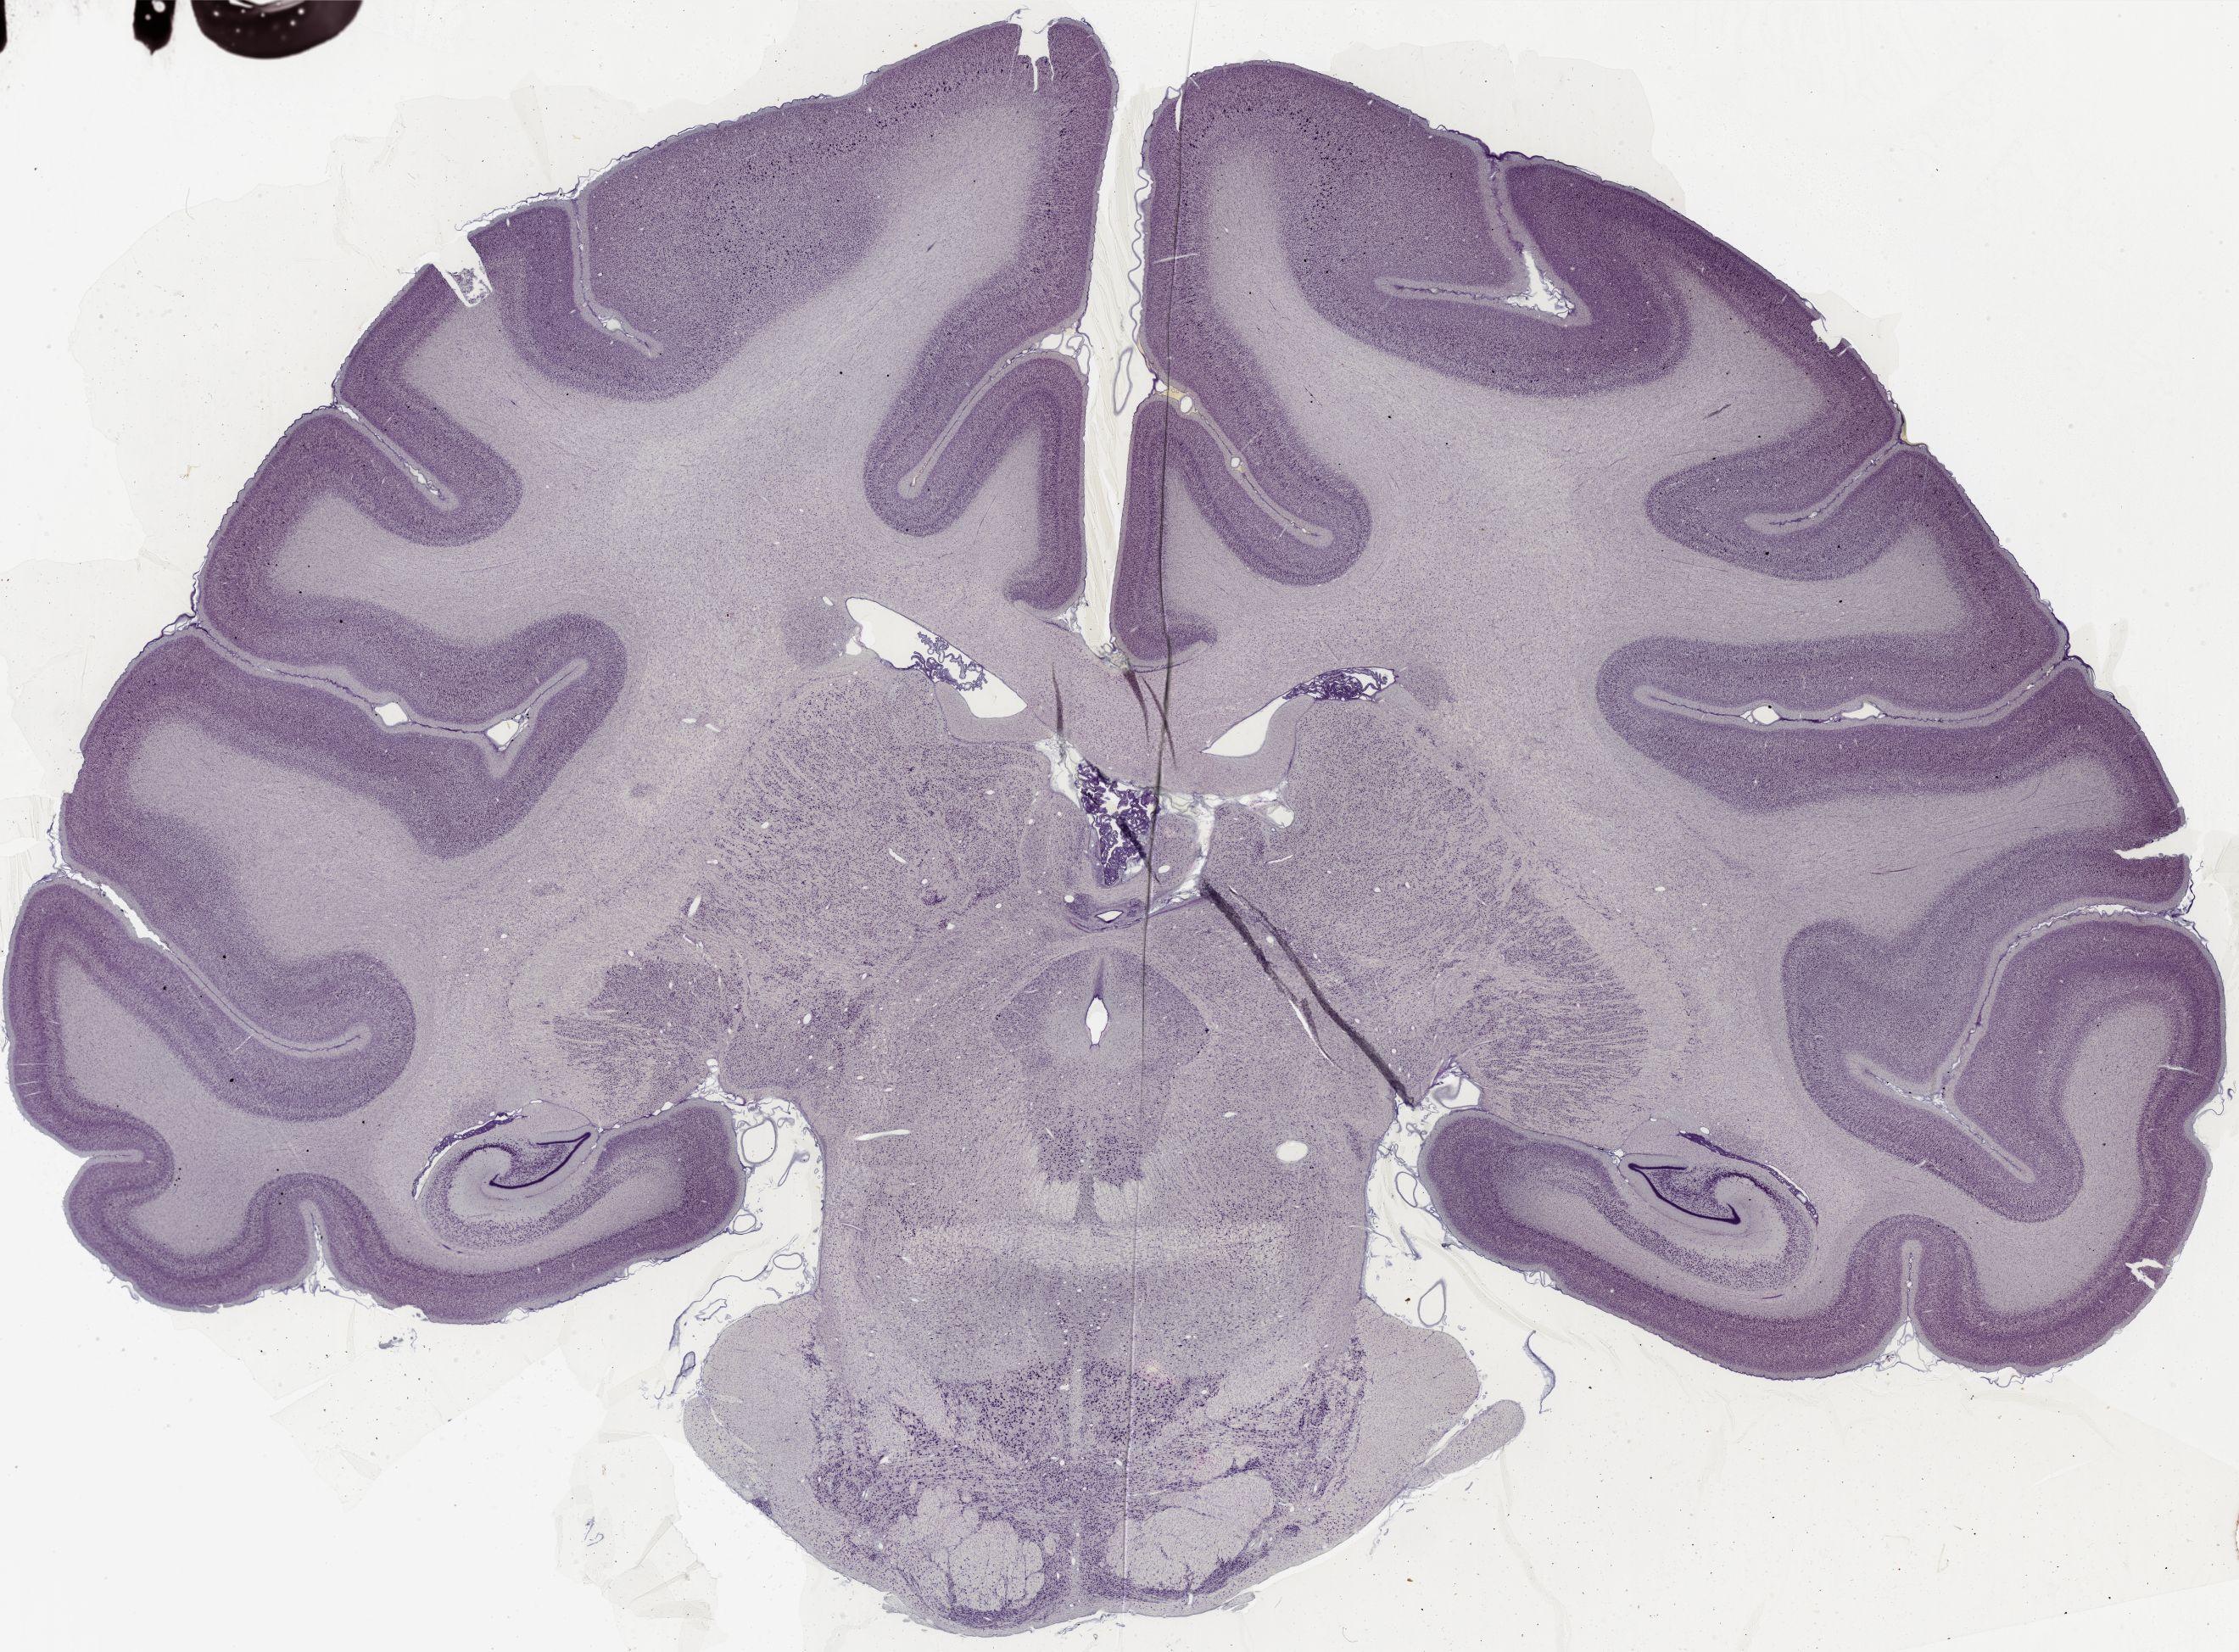

Datasets -> Macaca Mulatta -> Nissl, coronal, histo, Whole-Brain, adult [ Metadata ] · Source: Edward G. JonesDisplaying Sections 1 thru 40 of 56 Sections for this DatasetPages: 1 2 1339 - labeled 1301 - labeled 1251 - labeled 1201 - labeled 1151 - labeled 1102 - labeled 1051 - labeled 1040 - labeled 1020 - labeled 1006 - labeled 1001 - labeled 0982 - labeled 0975 - labeled 0958 - labeled 0951 - labeled 0941 - labeled 0924 - labeled 0920 - labeled 0901 - labeled 0894 - labeled 0878 - labeled 0875 - labeled 0859 - labeled 0851 - labeled 0845 - labeled 0824 - labeled 0823 - labeled 0801 - labeled 0800 - labeled 0785 - labeled 0781 - labeled 0771 - labeled 0770 - labeled 0732 - labeled 0721 - labeled 0720 - labeled 0701 - labeled 0682 - labeled 0680 - labeled 0666 - labeledPages: 1 2